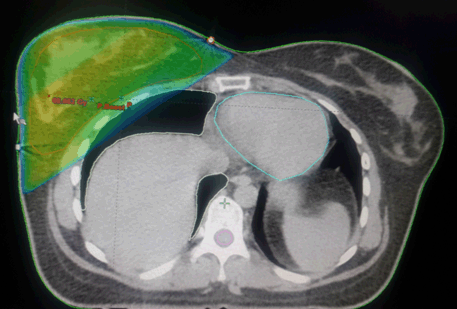

After the multidisciplinary consultation meeting, a breast-conserving surgery was performed and the lymph node dissection performed nine free lymph nodes and the final anapathological examination was in favor of a slightly differentiated ductal adenocarcinoma infiltrating grade III of Scarff-Bloom-Richardson grading system; triple negative. Subsequently, the patient was treated with three-cure of 5 fluorouracil, epiadriamycin and cyclophosphamide adjuvant chemotherapy and three docetaxel cures and then received external adjuvant radiotherapy 3D; a dose of 50 Gy in 25 sessions at 2 Gy by fraction, followed by a boost on the tumor bed by 10 Gy photons in five sessions (Figure 1). The films of the field involved were first examined carefully by the radiotherapist to assess the risk of breast irradiation.

Cursor on image to zoom/Click text to open image

Figure 1: Dosimetric image showing the distribution of the dose on the mammary gland.